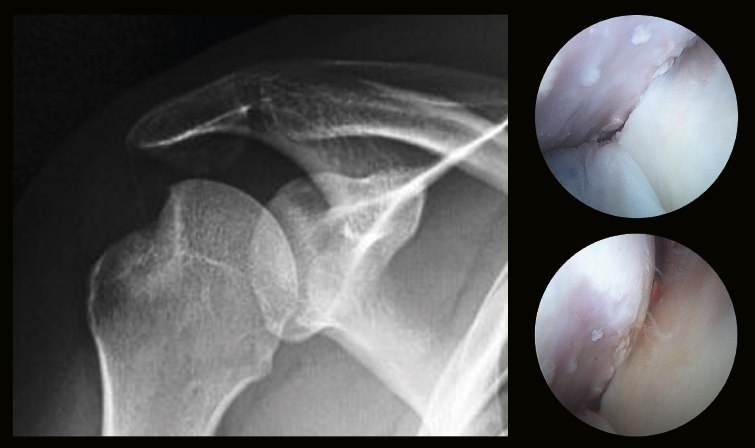

El defecto óseo en la cabeza humeral se mide en porcentajes con la fórmula (X/Y) × 100% en una radiografía o TAC axial, donde “Y” es el perímetro de cartílago articular de la cabeza humeral y “X” es el perímetro del defecto de la lesión de Hill-Sachs (LHS) (Figura 2). En los defectos óseos de la cabeza humeral, además de medir el tamaño, es importante valorar la orientación del defecto, fundamentalmente al realizar abducción y rotación externa. Lesiones de Hill-Sachs con un eje largo paralelo al borde glenoideo anterior suelen ser “lesiones enganchantes”, donde el defecto de la cabeza del hombro se engancha o encaja sobre el borde anterior de la glena en posición de abducción y rotación externa, predisponiendo a luxaciones y subluxaciones. Las lesiones de Hill-Sachs con el eje largo no paralelo al borde anterior de la glena no suelen engancharse al realizar abducción y rotación externa, “lesiones no enganchantes”(19,20)(Figura 3).

Figura 4. Distancia desde el margen medial de Hill-Sachs (HS) al margen medial foot print del manguito (línea azul) comparada con la medición del glenoid track (GT) (línea roja). A: lesión de HS on-track o no enganchante, LHS < GT; B: lesión HS off-track o enganchante, LHS > GT.

Itoi et al. estudiaron la relación anatómica exacta entre la cabeza humeral y la glenoides en diferentes posiciones críticas(23,24), surgiendo el concepto de glenoid track (GT), como el área de contacto de la cabeza humeral con la glena al desplazarse esta de inferomedial a superolateral al realizar un movimiento de abducción de 0, 30 y 90°, y rotación externa(25,26). El GT fue calculado por Yamamoto et al.(26) en cadáveres y su longitud era de 18,4 ± 2,5 mm, que corresponde al 84 ± 14% del área total de la glena (distancia desde el margen medial de la inserción del manguito rotador en la tuberosidad y el margen medial del área de contacto). Omori et al.(27) hacen la misma medición en un estudio dinámico en personas vivas y concluyen que el GT es del 84 ± 14% con el brazo en abducción de 90° y rotación externa, quedando el valor del 84% como el estándar para la medición de las lesiones con defecto óseo. Para saber si una lesión es on-track/off-track, es decir, que la lesión del Hill-Sachs esté dentro del recorrido de la cabeza sobre la glena (on-track) o fuera (off-track), debemos hacer la medición del GT con 3D-TAC comparando el hombro sano con el lesionado, de forma que: el ancho de la glena (D) en el hombro sano sin defecto óseo es del 100%, en el hombro lesionado con defecto en la glena (d) es D – d; por tanto, el GT = 0,84 × D – d. Esta medición se compara con la longitud de la lesión del Hill-Sachs medida en el corte coronal de la 3D-TAC desde el margen medial de la inserción del manguito hasta el borde medial de la LHS, de forma que nos podremos encontrar 2 situaciones (Figura 4):

- LHS on-track o no enganchable: tamaño de la longitud de la LHS es menor que la longitud de la GT (LHS < GT).

- LHS off-track o enganchable: LHS > GT.